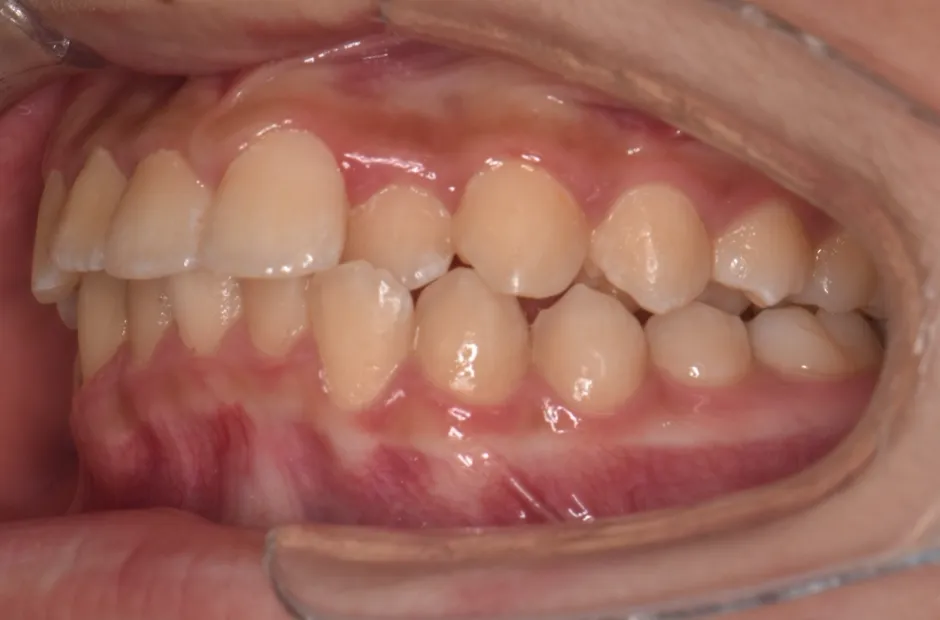

治療症例

ブラケット矯正

前歯部反対咬合

| 診断名・主訴 | 前歯部反対咬合 |

|---|---|

| 年齢・性別 | 14歳・男性 |

| 治療期間・回数 | 1年2か月 |

| 治療に用いた主な装置 | ブラケット矯正 |

| 抜歯部位 | なし |

| 治療費 | 60万円(税抜) |

| リスク・副作用 | 装置による違和感・疼痛・歯肉退縮・歯根吸収・虫歯のリスクなど |

治療前

治療後